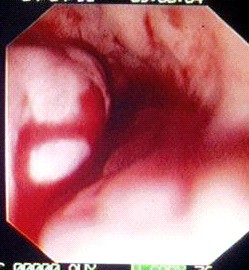

אנמנזה טובה ובדיקה פיזיקלית יכולות לספק אינפורמציה רבה על שאלות אלה. פירוט של האנמנזה והממצאים בבדיקה הפיזיקלית כפי שצוינו בתחילת פרק זה הם המרכיבים העיקריים באבחנה. לכל חולה כזה יש לבצע בדיקות דם מקיפות, כולל תפקודי כבד, תפקודי קרישה ותפקודי כליות. לאחר הערכה ראשונית וטיפול במצב החד, יש לבצע אנדוסקופיה על מנת לברר מה מקור הדימום ולראות האם לחולה יש דליות מדממות (תמונה 2.10). אם לחולה יש דליות מדממות אפשר להזריק לתוכן חומר מטרש ועל-ידי כך לעצור את הדימום. אפשר גם לבצע בליעת בריום על מנת להדגים דליות, כיבים פפטים, בקעים בסרעפת וכו'. ל- 52% מהחולים בעלי דליות יש גם כיבים פפטים. רק ב- 50% מהחולים בעלי דליות הוושט ניתן לראות דליות בבליעת בריום ולכן העדיפות המוחלטת של האזופגוסקופיה לבירור דליות.